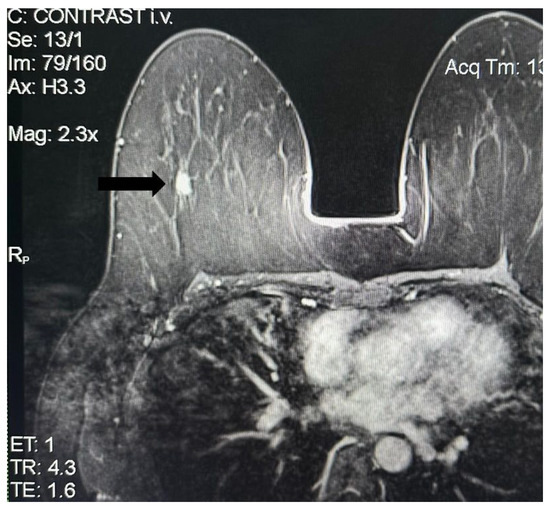

Eight years later, in May 2023, she presented her annual imagistic report where the following was described: abdomen and pelvic MRI—para-aortic left adenopathies with conglomerate aspect, the biggest measuring maximum 23/20 mm and 12/10 mm with features highly suggestive of an oncological process; breast ultrasound and MRI—right breast, supero-external quadrant, hour 10, at approximately 5 cm distance from the mammary papilla, the presence of a hypoechogenic nodule with microcalcifications, irregular margins, measuring 1.33/1.18/1.27 cm (Figure 1 and Figure 2).

Figure 2. US image showing right breast nodule.